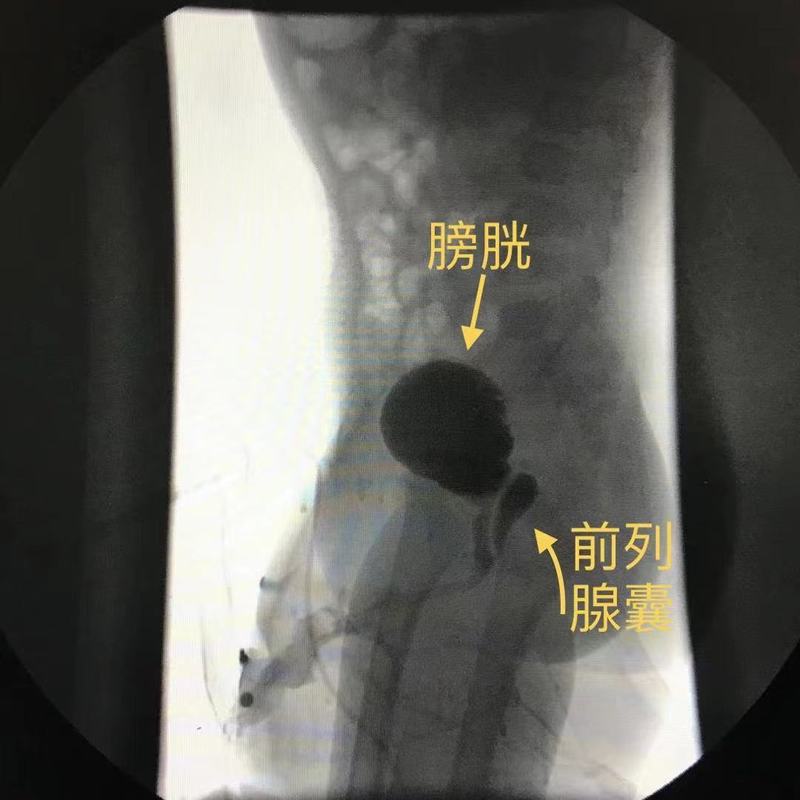

尿道下裂與前列腺囊

一.什么是前列腺囊前列腺囊是位于后尿道前列腺部的憇室樣結(jié)構(gòu),開(kāi)囗于精阜。單純前列腺囊發(fā)病率低,在重度尿道下裂患兒中,發(fā)病率可高達(dá)50%以上。考慮是發(fā)育過(guò)程中苗勒氏管退化不全或雄性激素不足導(dǎo)致尿生殖竇分化異常所致,簡(jiǎn)單來(lái)說(shuō),就是一種發(fā)育異常。二.前列腺囊的臨床表現(xiàn)1.反復(fù)附睪炎。表現(xiàn)為經(jīng)常陰囊紅腫,睪丸疼痛。正常狀態(tài)下,睪丸產(chǎn)生精子,儲(chǔ)存在附睪,通過(guò)輸精管開(kāi)口于前列腺部的精阜上。但由于前列腺囊的存在,輸精管通常開(kāi)口于前列腺囊上,當(dāng)排尿時(shí)尿液進(jìn)入前列腺囊,囊內(nèi)的尿液通過(guò)輸精管反流進(jìn)入附睪,引發(fā)感染,造成附睪炎,可一側(cè)或雙側(cè)發(fā)作。2.反復(fù)泌尿道感染。如果進(jìn)入囊內(nèi)的尿液排出不暢,前列腺囊不斷增大,會(huì)壓迫膀胱尿道出口,造成排尿困難,反復(fù)泌尿道感染。3.如果囊內(nèi)積存尿液多,還會(huì)排尿后滴瀝,囊內(nèi)形成結(jié)石。4.成年后精子活力及數(shù)量下降,癌變等。三.前列腺囊的診斷通過(guò)超聲檢查,排尿性膀胱尿道造影,CT或MR,膀胱尿道鏡檢查可以確診。四.關(guān)于前列腺囊的治療前列腺囊的大小并非前列腺囊切除術(shù)的絕對(duì)標(biāo)準(zhǔn)。臨床主要根據(jù)患者的臨床表現(xiàn),結(jié)合影像學(xué)資料及膀胱尿道鏡檢查,綜合考慮。因?yàn)槟壳皝?lái)講,腹腔鏡下前列腺囊切除術(shù)大部分不可避免會(huì)切斷輸精管。1.單純反復(fù)附睪炎,囊不大的,可以結(jié)扎切斷同側(cè)輸精管。2.如果尿道下裂術(shù)后有尿道狹窄的,先處理狹窄,解除梗阻。3.反復(fù)附睪炎,尿路感染,膿尿,血尿,經(jīng)抗感染治無(wú)效,再考慮選擇手術(shù)治療。五.合并前列腺囊的注意問(wèn)題合并有前列腺囊的患兒,平時(shí)要注意尿線,排尿時(shí)間,有無(wú)排尿困難及排尿用力,有無(wú)與排尿相關(guān)的癥狀,如膀胱區(qū)疼痛,尿頻尿急,尿痛,尿液混濁,血尿等不適,有無(wú)陰囊紅腫熱痛,發(fā)現(xiàn)異常,及時(shí)就診。六.前列腺囊的隨訪合并前列腺囊的尿道下裂術(shù)后,需術(shù)后1,3,6個(gè)月,術(shù)后1年,2年復(fù)查,視排尿情況及有無(wú)癥狀來(lái)調(diào)整復(fù)查時(shí)間。青春期前后,婚育期需要復(fù)查。參巧文獻(xiàn)1.楊洋,張濰平,孫寧等.腹腔鏡技術(shù)在小兒尿道下裂合并前列腺囊治療中的應(yīng)用,中華小兒外科雜志,2017年6月第38卷第6期:420-4232.涂磊,趙夭望,彭潛龍等,膀胱尿道鏡檢術(shù)診治重度尿道下裂合并前列腺囊的單中心臨床研究,臨床小兒外科雜志,2018年7期